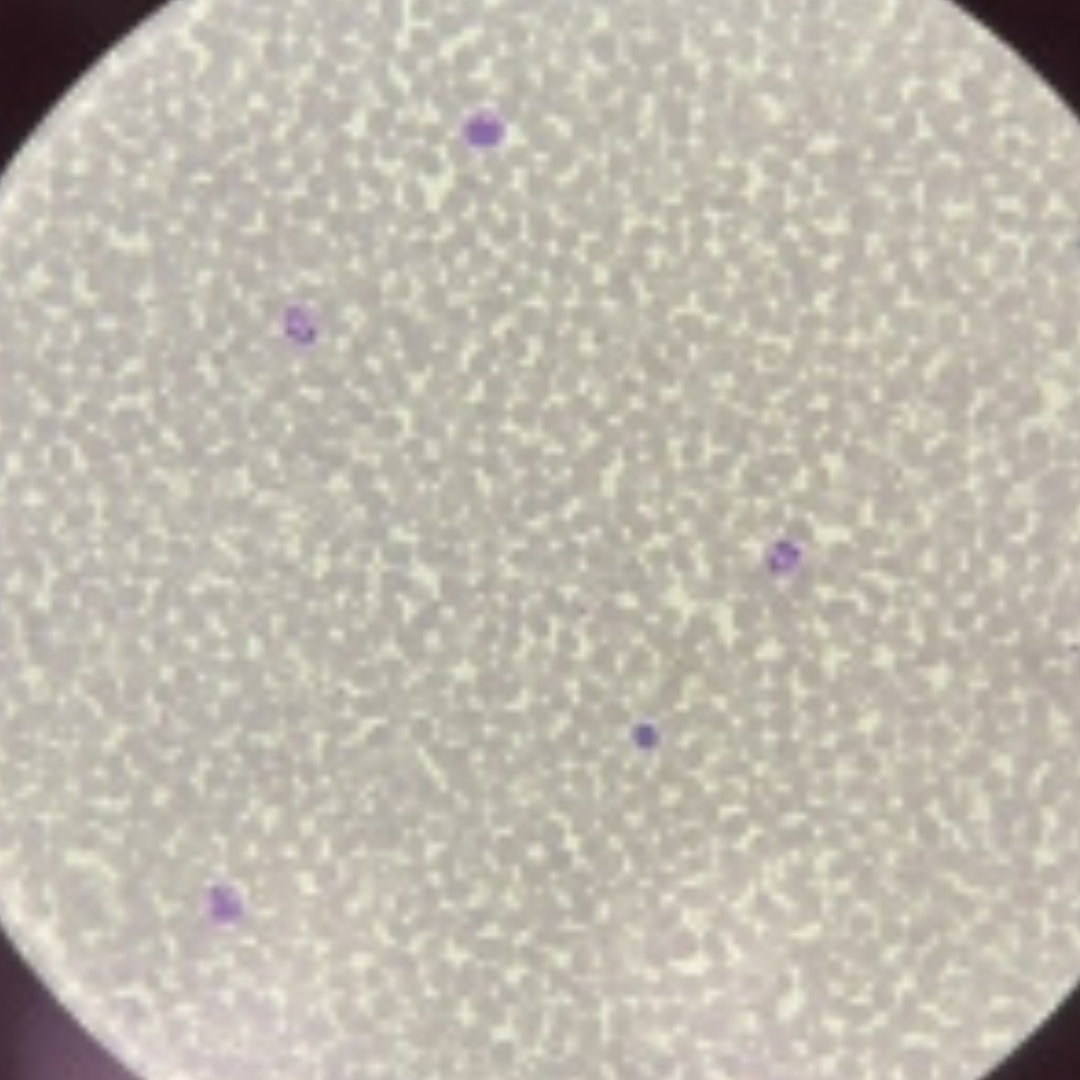

Blood

Blood